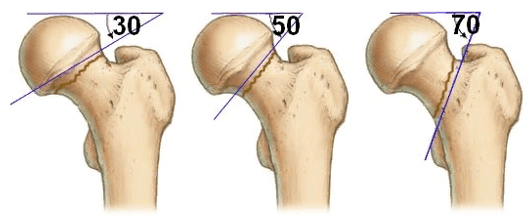

Суть метода состоит в устранении патологического разворота кости относительно сустава, провоцирующего проблемы с ходьбой. Анормальный разворот в медицине называется ротационной дисплазией. Для патологии характерна избыточная антеторсия, сопровождающаяся децентрацией бедренной головки по отношению к вертлужной впадине. Клиническая ситуация отражается в основном на походке: так как нога ротирована кнутри, походка приобретает типичные признаки косолапости. Такое нарушение также может предрасполагать к вывиху ТБС, появлению боли. Бедренная деротационная хирургия предназначена для сокращения угла антеторсии до нормальных показателей. Эффект достигается за счет проведения подвертельной поперечной остеотомии с фиксацией восстановленной области (спицами, винтами, пр.) для ее благополучного сращения в непорочной позиции.

Операции, направленные на создание опороспособного безболезненного сустава, преимущественно применяются при coxa vara/valga, неоартрозах шейки бедра, застарелых шеечных переломах, врожденных вывихах, остеоартрозах. Задачу восстановления опорной функции, удобной для ходьбы и стояния, зачастую решают путем изменения оси шейки бедра. Измененный шеечно-диафизарный угол меняет точку опоры головки, которая изначально была патологической, на несколько миллиметров (до 15 мм). Такой подход благоприятствует не только возобновлению опороспособности, но и декомпрессии сустава, сокращению болевой симптоматики. Перерезание бедренной кости проводят самым целесообразным способом, который выбирается на основании индивидуальных рентгенологических данных.